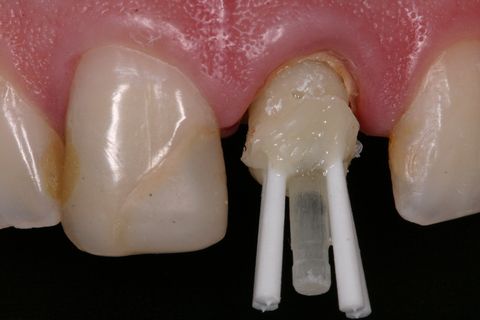

Inserção dos pinos acessórios na resina

Isolou-se o conduto radicular com óleo mineral e inseriu-se a resina composta (Fill Magic NT Premium, Coltene-Vigodent, Brasil) sobre o remanescente dentário com auxílio de uma espátula suprafill #1/2 (Figuras 5 e 6). Após o preenchimento do conduto com resina, foi inserido o pino Exacto cônico e os pinos acessórios previamente silanizados (Silano, Angelus, Brasil) e com a aplicação do adesivo (Fusion Duralink, Angelus, Brasil) (Figuras 7, 8 e 9). Em seguida, promoveu-se a fotoativação inicial do conjunto pino-resina por 20 segundos.